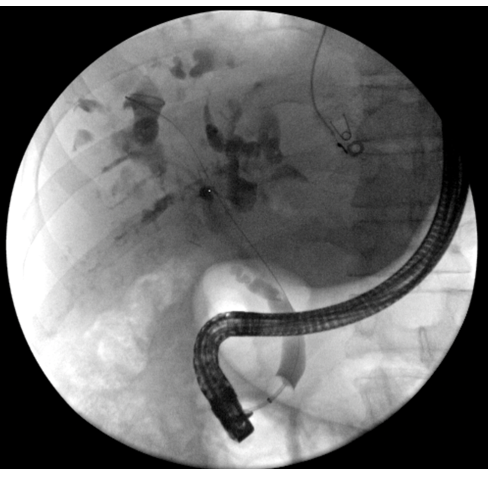

CBD stricture

19

Q

A

long CBD stricture

20

21